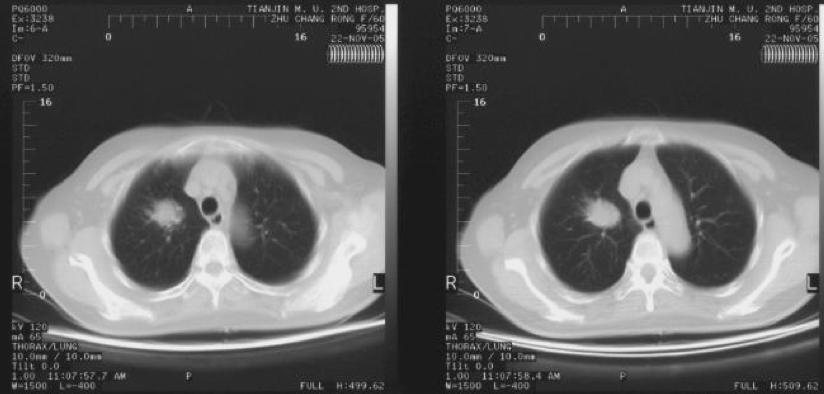

碘125粒子源植入治疗右肺周围性肺癌

术前

术后6个月疗效达到完全缓解